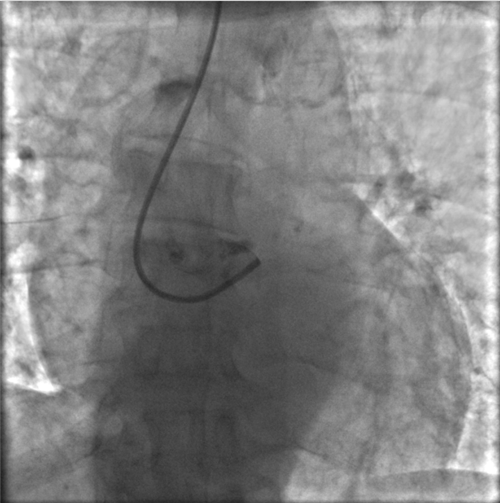

左主干完全閉塞

小心操作導(dǎo)絲及導(dǎo)管,艱難到達(dá)主動脈根部,但導(dǎo)管難以“到位”左冠口,“冒煙”見左主干居然完全閉塞了。